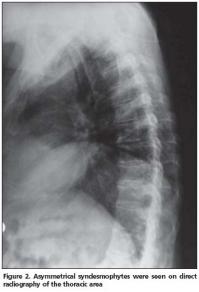

Anterior longitudinal ligament calcification, fusion of multiple facet joints and atypical syndesmophytes were found on cervical spine X-rays (Figure 1) and coarse, asymmetrical syndesmophytes were seen on thoracic (Figure 2) and lumbar spine (Figure 3) X-rays. No abnormalities suggesting PsA or gout were seen on hand and foot radiographs. The magnetic resonance imaging (MRI) of the sacroiliac joint and computerized tomography (CT) of atlanto-axial joint were normal.

Another striking radiologic finding in our patient was that cervical spine involvement was on the foreground. Queiro et al. reported the cervical spine involvement in HLA-B27- negative PsSpA patients to be 51%[13]. Cervical spine involvement in PsA is known to be seen more commonly in patients presenting with psoriatic lesions on hairy skin[12]. The majority of skin lesions were localized on the hairy skin in our patient. Radiographic abnormalities are not sufficiently sensitive and specific for the diagnosis of gout. Only 45% of patients with gout manifest radiographic bone changes, and then only six to eight years after the initial attack. The radiographic hallmarks of gout are normal mineralization, joint space preservation, sharply marginated erosions with sclerotic borders, overhanging edges, and asymmetric polyarticular distribution[14]. Radiologic evaluation of our patient did not reveal any of these images.